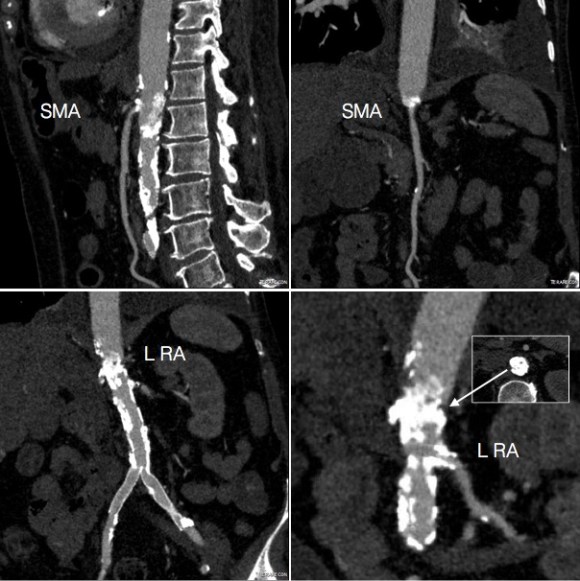

Examination was remarkable for a well nourished young woman in distress with epigastric tenderness. Inflammatory markers were normal and she was on methotrexate and tocilizumab. CTA (above) and duplex showed severe stenoses affecting the origins of the celiac axis and superior mesenteric artery. A composite of the centerlines through these showed the arteries to be critically narrowed at their origins (below), along with a mild to moderate stenosis of the aorta (above). No active inflammation could be seen.

The anterior view of the 3DVR images of her CT showed an absence of collateralization via the inferior mesenteric artery and Arc of Riolan.

This could account for her postprandial abdominal pain which was midabdominal, but the midsternal chest pain was difficult to explain. A cardiac cause had been ruled out at her home institution. It was on the lower part of the sternum and bordered the epigastrium. Through my work with median arcuate ligament syndrome, it was not unusual to have chest pain be part of the pain syndrome which comes about through the compression of the celiac plexus by the median arcuate ligament (reference), and treated effectively with the division of the median arcuate ligament and celiac plexus neurolysis.